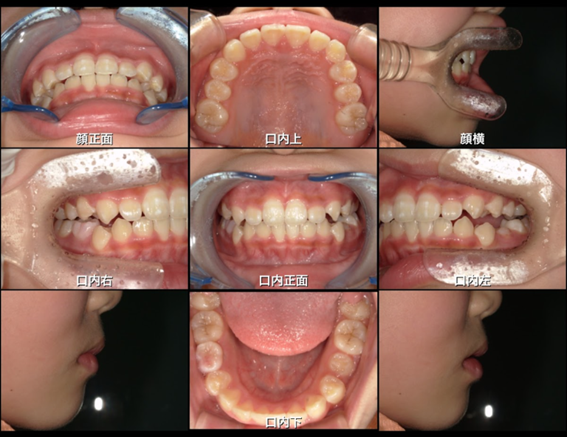

| 患者年齢 | 7歳 |

|---|---|

| 主訴(治療動機) | 上の前歯の逆被蓋(上の前歯1本だけ内側に引っ込んでいる) |

| 治療内容 | MRC矯正 |

| 治療期間 | 3年(治療途中) |

| 治療費用 | 407,000円 |

| リスク、副作用 | マウスピースの装着方法や装着時間が適切でない場合、治療計画通りに歯が動かない場合があります。 矯正治療終了後は後戻りの可能性があるため、保定装置(リテーナー)の装着が必要です。 |

| ドクターからのコメント | 前歯の逆被蓋は早期に改善しましたが、歯列全体をキレイにしたいとのご希望で、治療を継続中です。 |